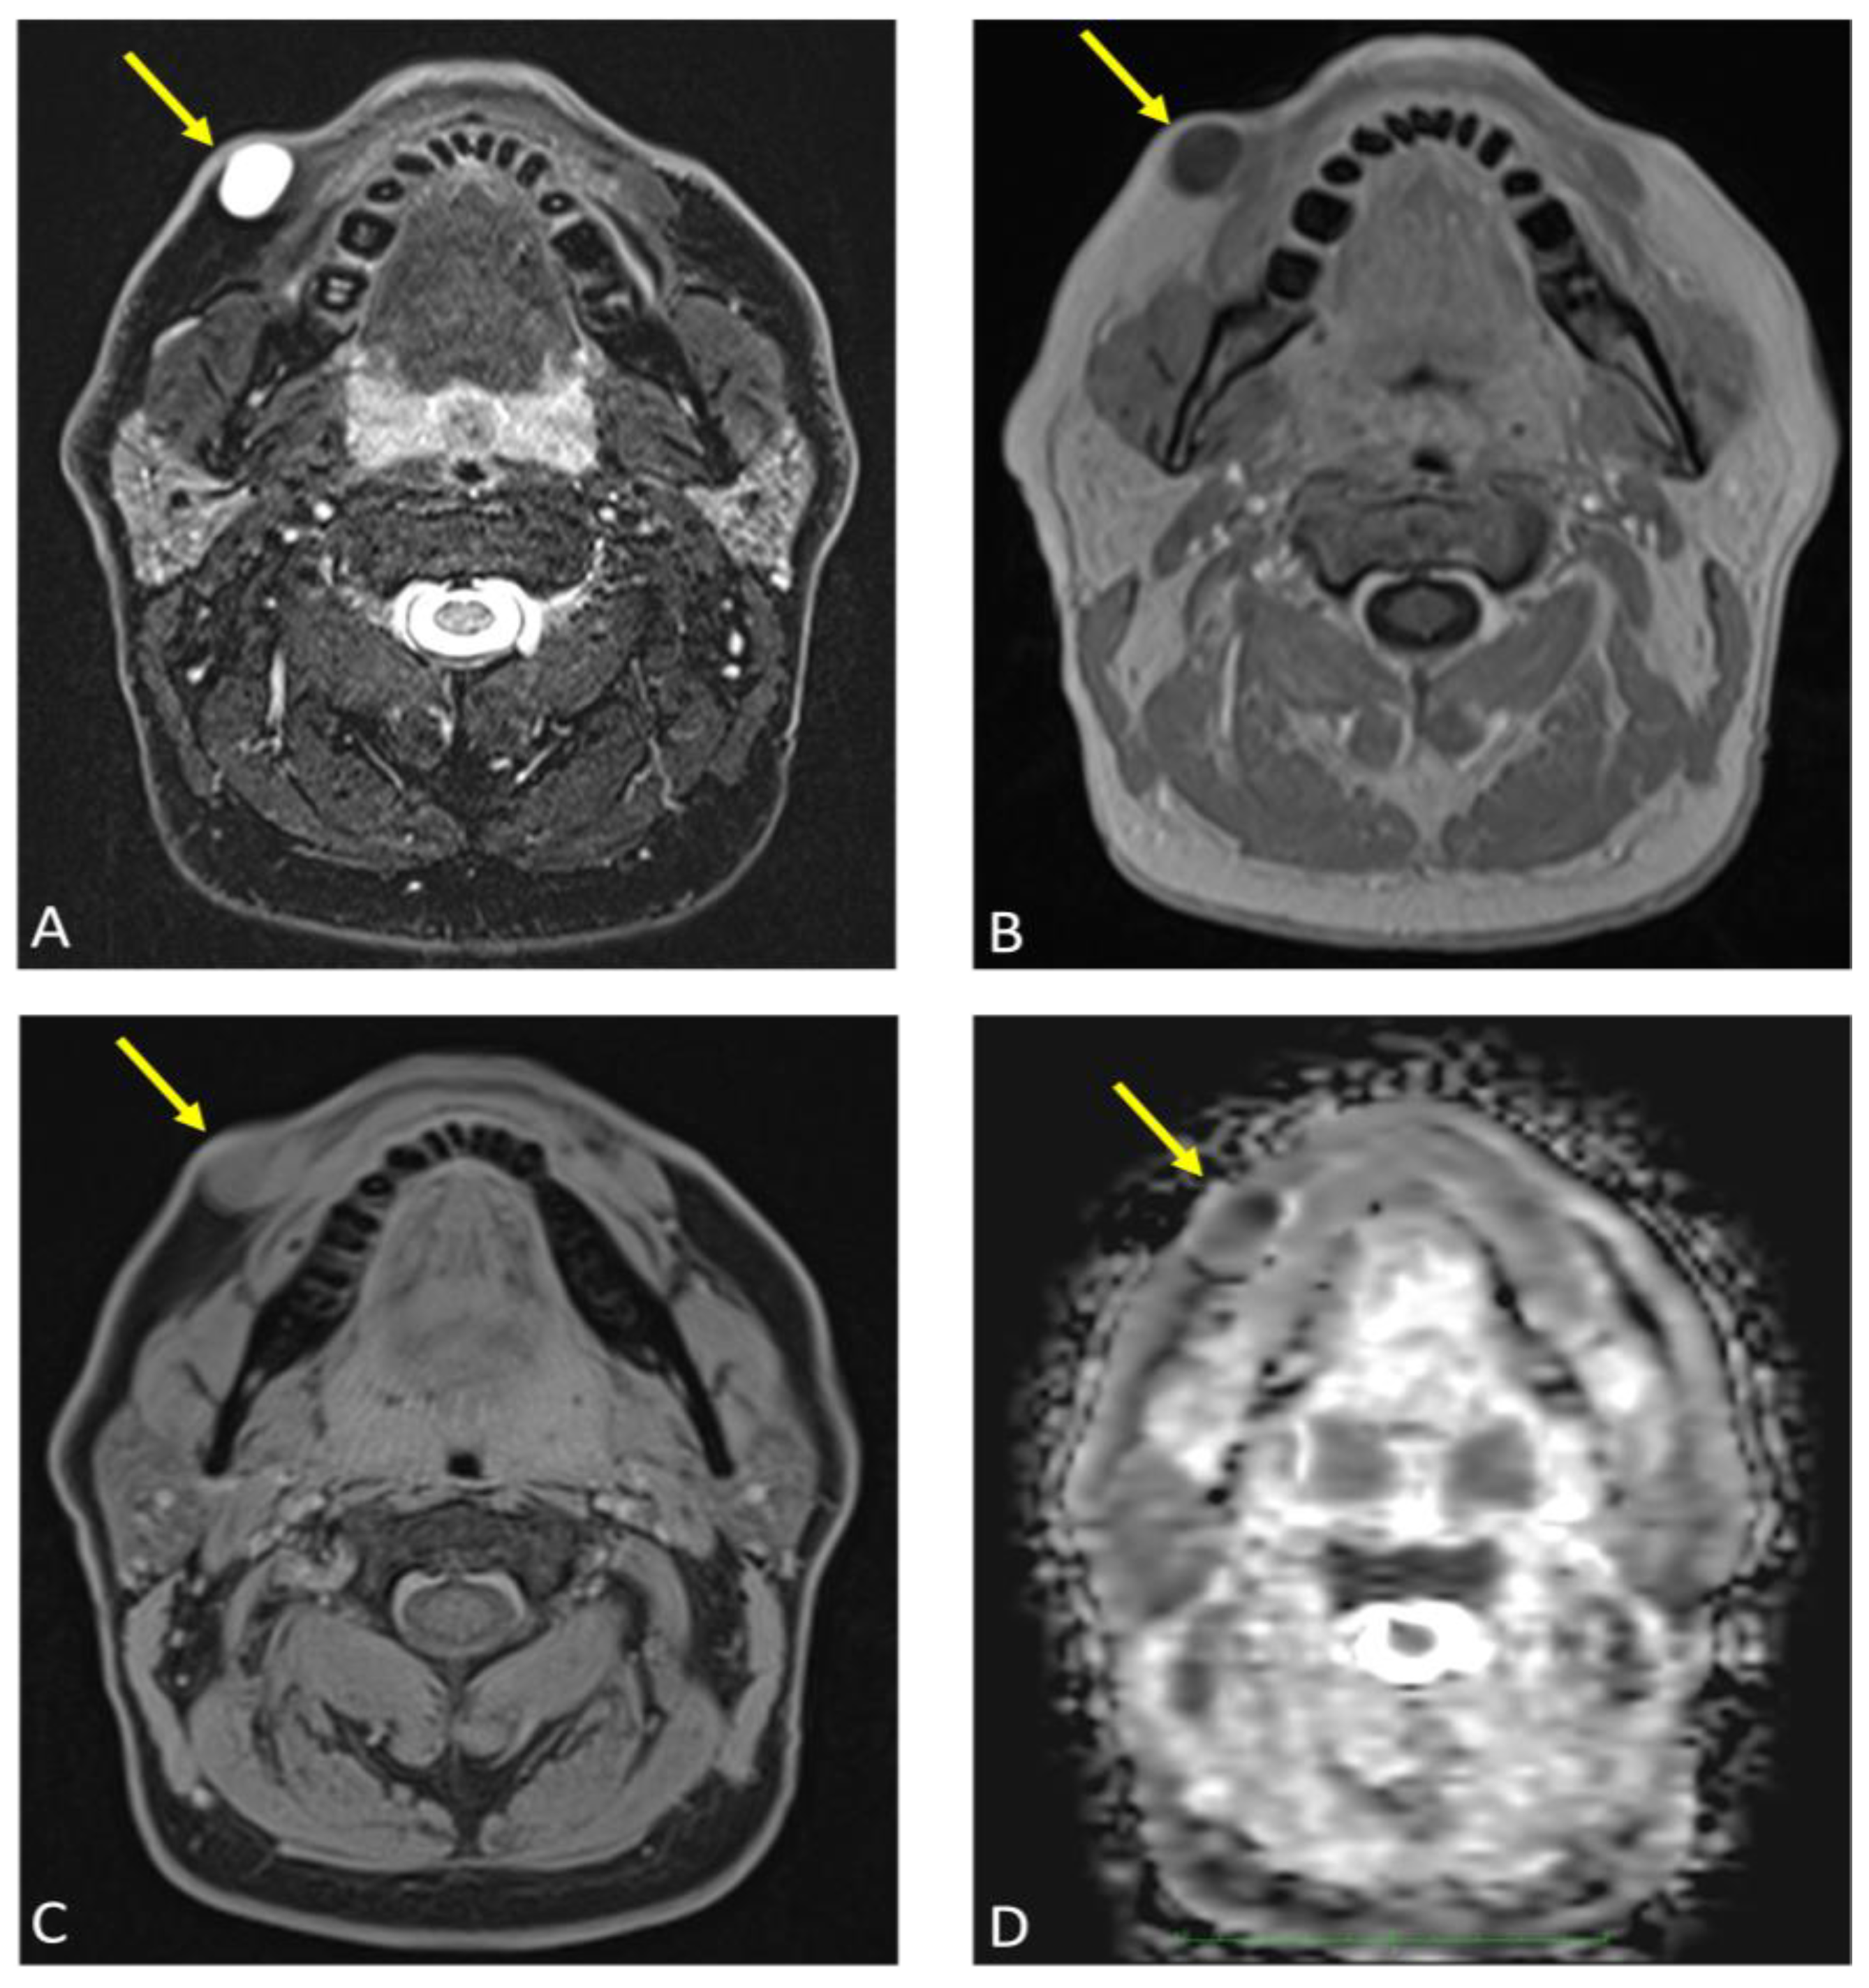

Axial reconstructions of the lesion (arrow) are displayed in multiple MR sequences: (A) T2-weighted turbo spin echo (TSE) Dixon, (B) T1-weighted volumetric interpolated breath-hold examination (VIBE) Dixon, (C) T1-weighted Star Volumetric Interpolated Breath-hold Examination (StarVIBE) Dixon technique, and (D) diffusion-weighted imaging (DWI). No significant contrast enhancement was noted in the lesion’s capsule, although there was a slight increase in protein concentration and isotropic diffusion restriction. These images collectively illustrate the lesion’s characteristics and contribute to the comprehensive assessment of its anatomical features and potential implications for the diagnosis and treatment of an epidermoid cyst.